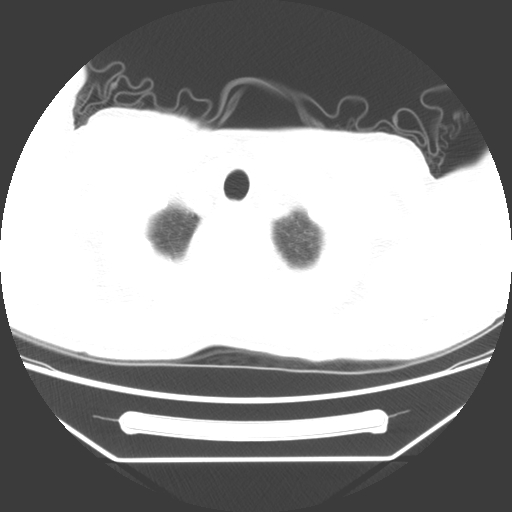

病人55岁,咳嗽,胸闷

忘了传病史了,病人55岁,咳嗽,胸闷

此病人我并没有见到,病史没有得到更详细,但此病人据说有发低热,请教各位老师,此病人像不像卡氏肺囊虫肺炎